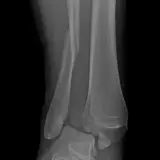

Over 2,100 interactive radiology cases, curated by radiologists for your level of training. Scroll, window, and view cases full screen — just like on PACS. Click linked findings in each writeup to jump straight to them on the image. Cases include sample reports, a focused discussion section, original illustrations, and videos.

Casos totalmente interactivos con las herramientas que esperaría de un PACS: scroll, ventana, zoom, pan, mediciones, ROI y modo de pantalla completa.

• Anotaciones enlazadas

Anotaciones extensas resaltan los hallazgos clave directamente sobre los casos. Haga clic en los hallazgos enlazados dentro de la descripción del caso para saltar a su ubicación exacta en el estudio.

Aprenda con eficiencia gracias a hallazgos de imagen anotados e ilustraciones